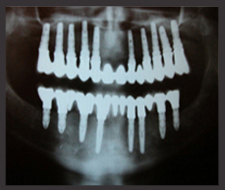

We need to see the patients and their x-rays before we can give a decent quotation.

Dental implants are like artificial roots of theet which are placed into the jaw. Dental implants are giving the support for crowns, bridges and removable dentures. This is a wonderful solution, because we can implant the artificial root into the place of the lost tooth thus after healing it can take over the original function.

Usually it is hard to tell the difference between the original tooth and the implant supported crowns.